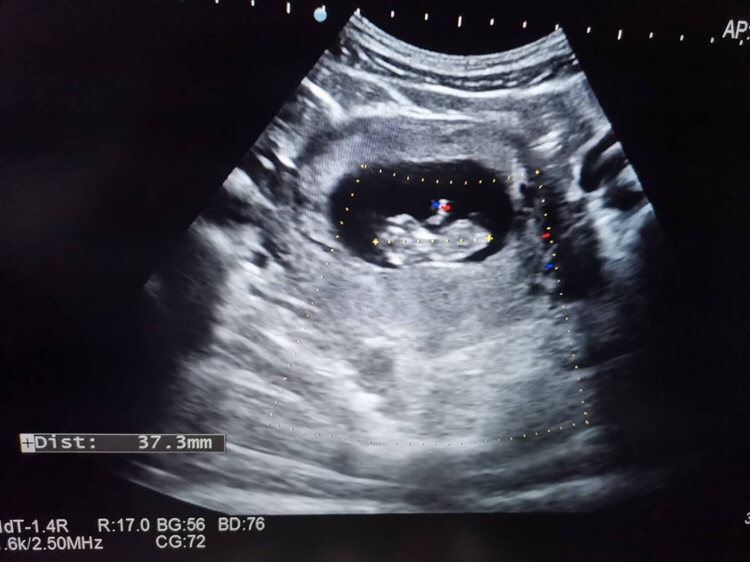

孕12周+5天